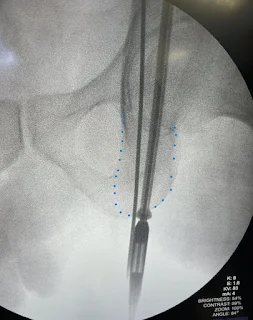

4. A long guidewire is inserted and its placement confirmed utilizing fluoroscopy.

- Obturator outlet view – confirms that you are staying within the posterior column and staying medial on it

- Rotate C-arm 45 degrees towards affected side and 20-30 degrees towards feet

- Iliac oblique view – confirms that the screw is extra-articular

- Rotate C-arm 45 degrees away from affected side